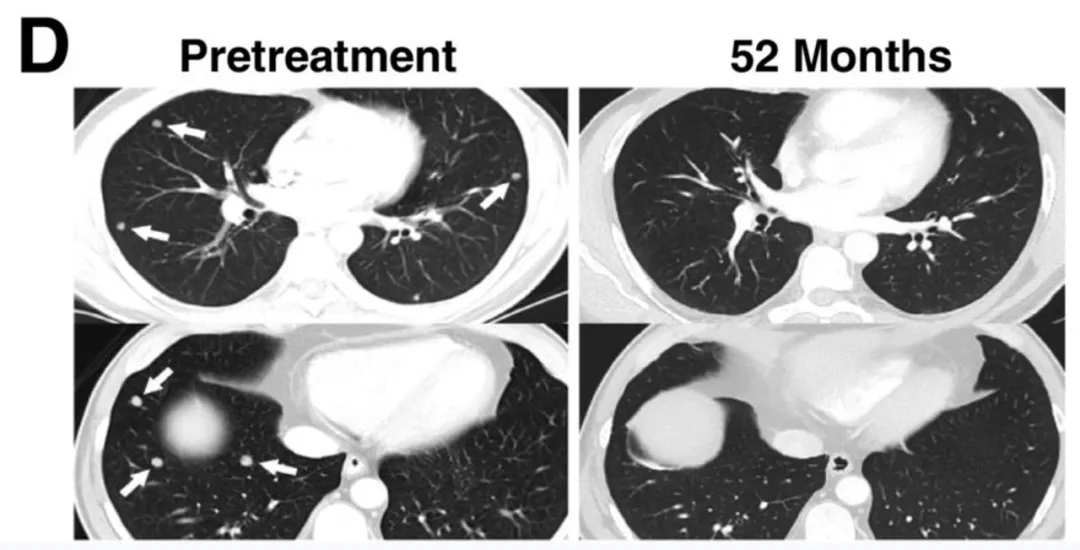

值得关注的是,CT及放射学检查清晰记录了典型患者的肿瘤消退情况:29号患者的肝脏和肺部多发转移灶完全消退(详见下图C/D),疗效维持54个月以上。